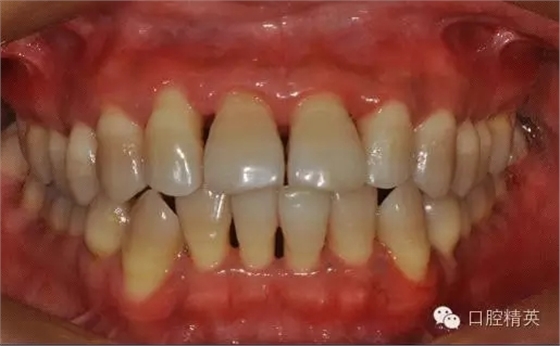

本病例 :女 34歲,主訴刷牙出血,覺牙齒輕度松動一年。

檢查見大量齦上及齦下結(jié)石,探診出血,牙周袋較深,32-42 II度松動。X線片顯示牙槽骨水平吸收。

診斷:成人慢性廣泛性中度牙周炎。

治療前: